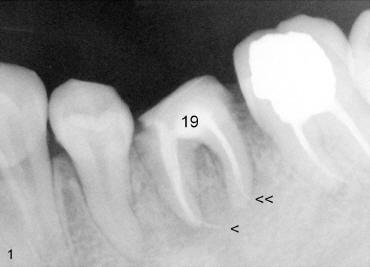

A 31-year-old otherwise healthy Chinese lady has had discomfort since RCT was done for the tooth #19 in home country ~2 years ago (Fig.1). Gutta percha (GP) appears to extrude both in mesial (<) and distal (<<) canals, surrounded by periapical radiolucency (PARL). Two carpules of 2% Lidocaine with 1:100,000 Epinephrine are used for RCT retreat. The patient does not experience any sharp pain during the first injection. Two rubber dams are used due to the short clinical crown of #19 (Fig.2,3). Fig.2 shows master cones (30/.06 M, 40/.06 D) after removal of existing gutta percha using Chloroform. It appears that extruded mesial GP remains outside the apex (< in Fig.2). It is confirmed after removing master cones (< in Fig.3). Working length is controlled by Apex locator during canal re-shaping using GT rotary files. In attempt to remove apparent GP in mesial canal(s) and extruded one outside the apex, #15 hand file is reused at WL+1mm with Chloroform for one or twice for each canal. After adjusting distal GP length, cold lateral condensation is finished with AH26 plus paste and pre-existing PFM crown is recemented (Fig.4). It is apparent that the previously extruded GP is not removed (< in Fig.4).

In fact, the traditional X-ray can also show the coronal portion of the abnormal communication (Fig.1). One or two months later, paresthesia disappears with occasional mild pain, reported by the patient. She has not returned for follow-up.